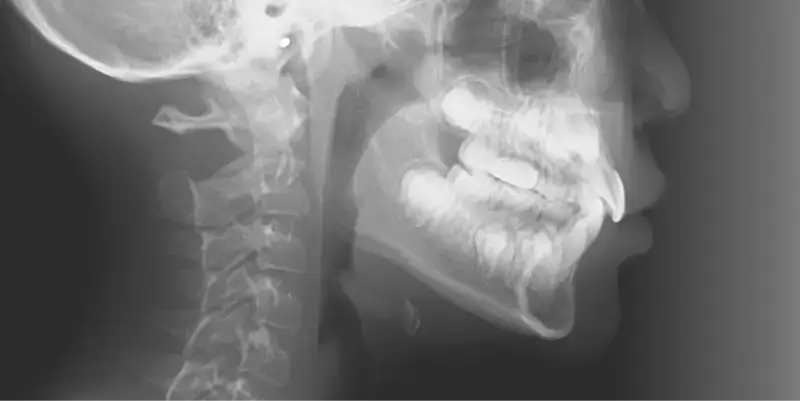

兒童早期矯正,又稱為「預防性矯正」或「第一階段矯正」,指的是在孩子乳牙或混合牙期(約7~10歲)時,就針對牙齒排列、咬合不正、牙弓發育等問題提前介入的矯正治療。 目的不只是「把牙齒排整齊」,更重要的是引導上下顎正常發育,減少未來拔牙、正顎手術的機率,讓恆牙有足夠空間健康萌發。

相當於國小低至中年級,這時會開始進到乳牙換成恆牙的階段,也是牙齒移動速度快的時期,在這個階段接受矯正能夠擁有良好的矯正效率,因此也被定義為「兒童矯正的黃金期」。